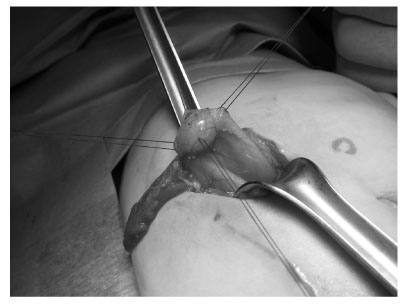

Fig. 3

Operative finding of gastric duplication which was located at the greater curvature, distal part of the stomach, measuring about 1 cm in diameter.

jkaps-18-35-g003.jpg

Fig. 3 Operative finding of gastric duplication which was located at the greater curvature, distal part of the stomach, measuring about 1 cm in diameter.